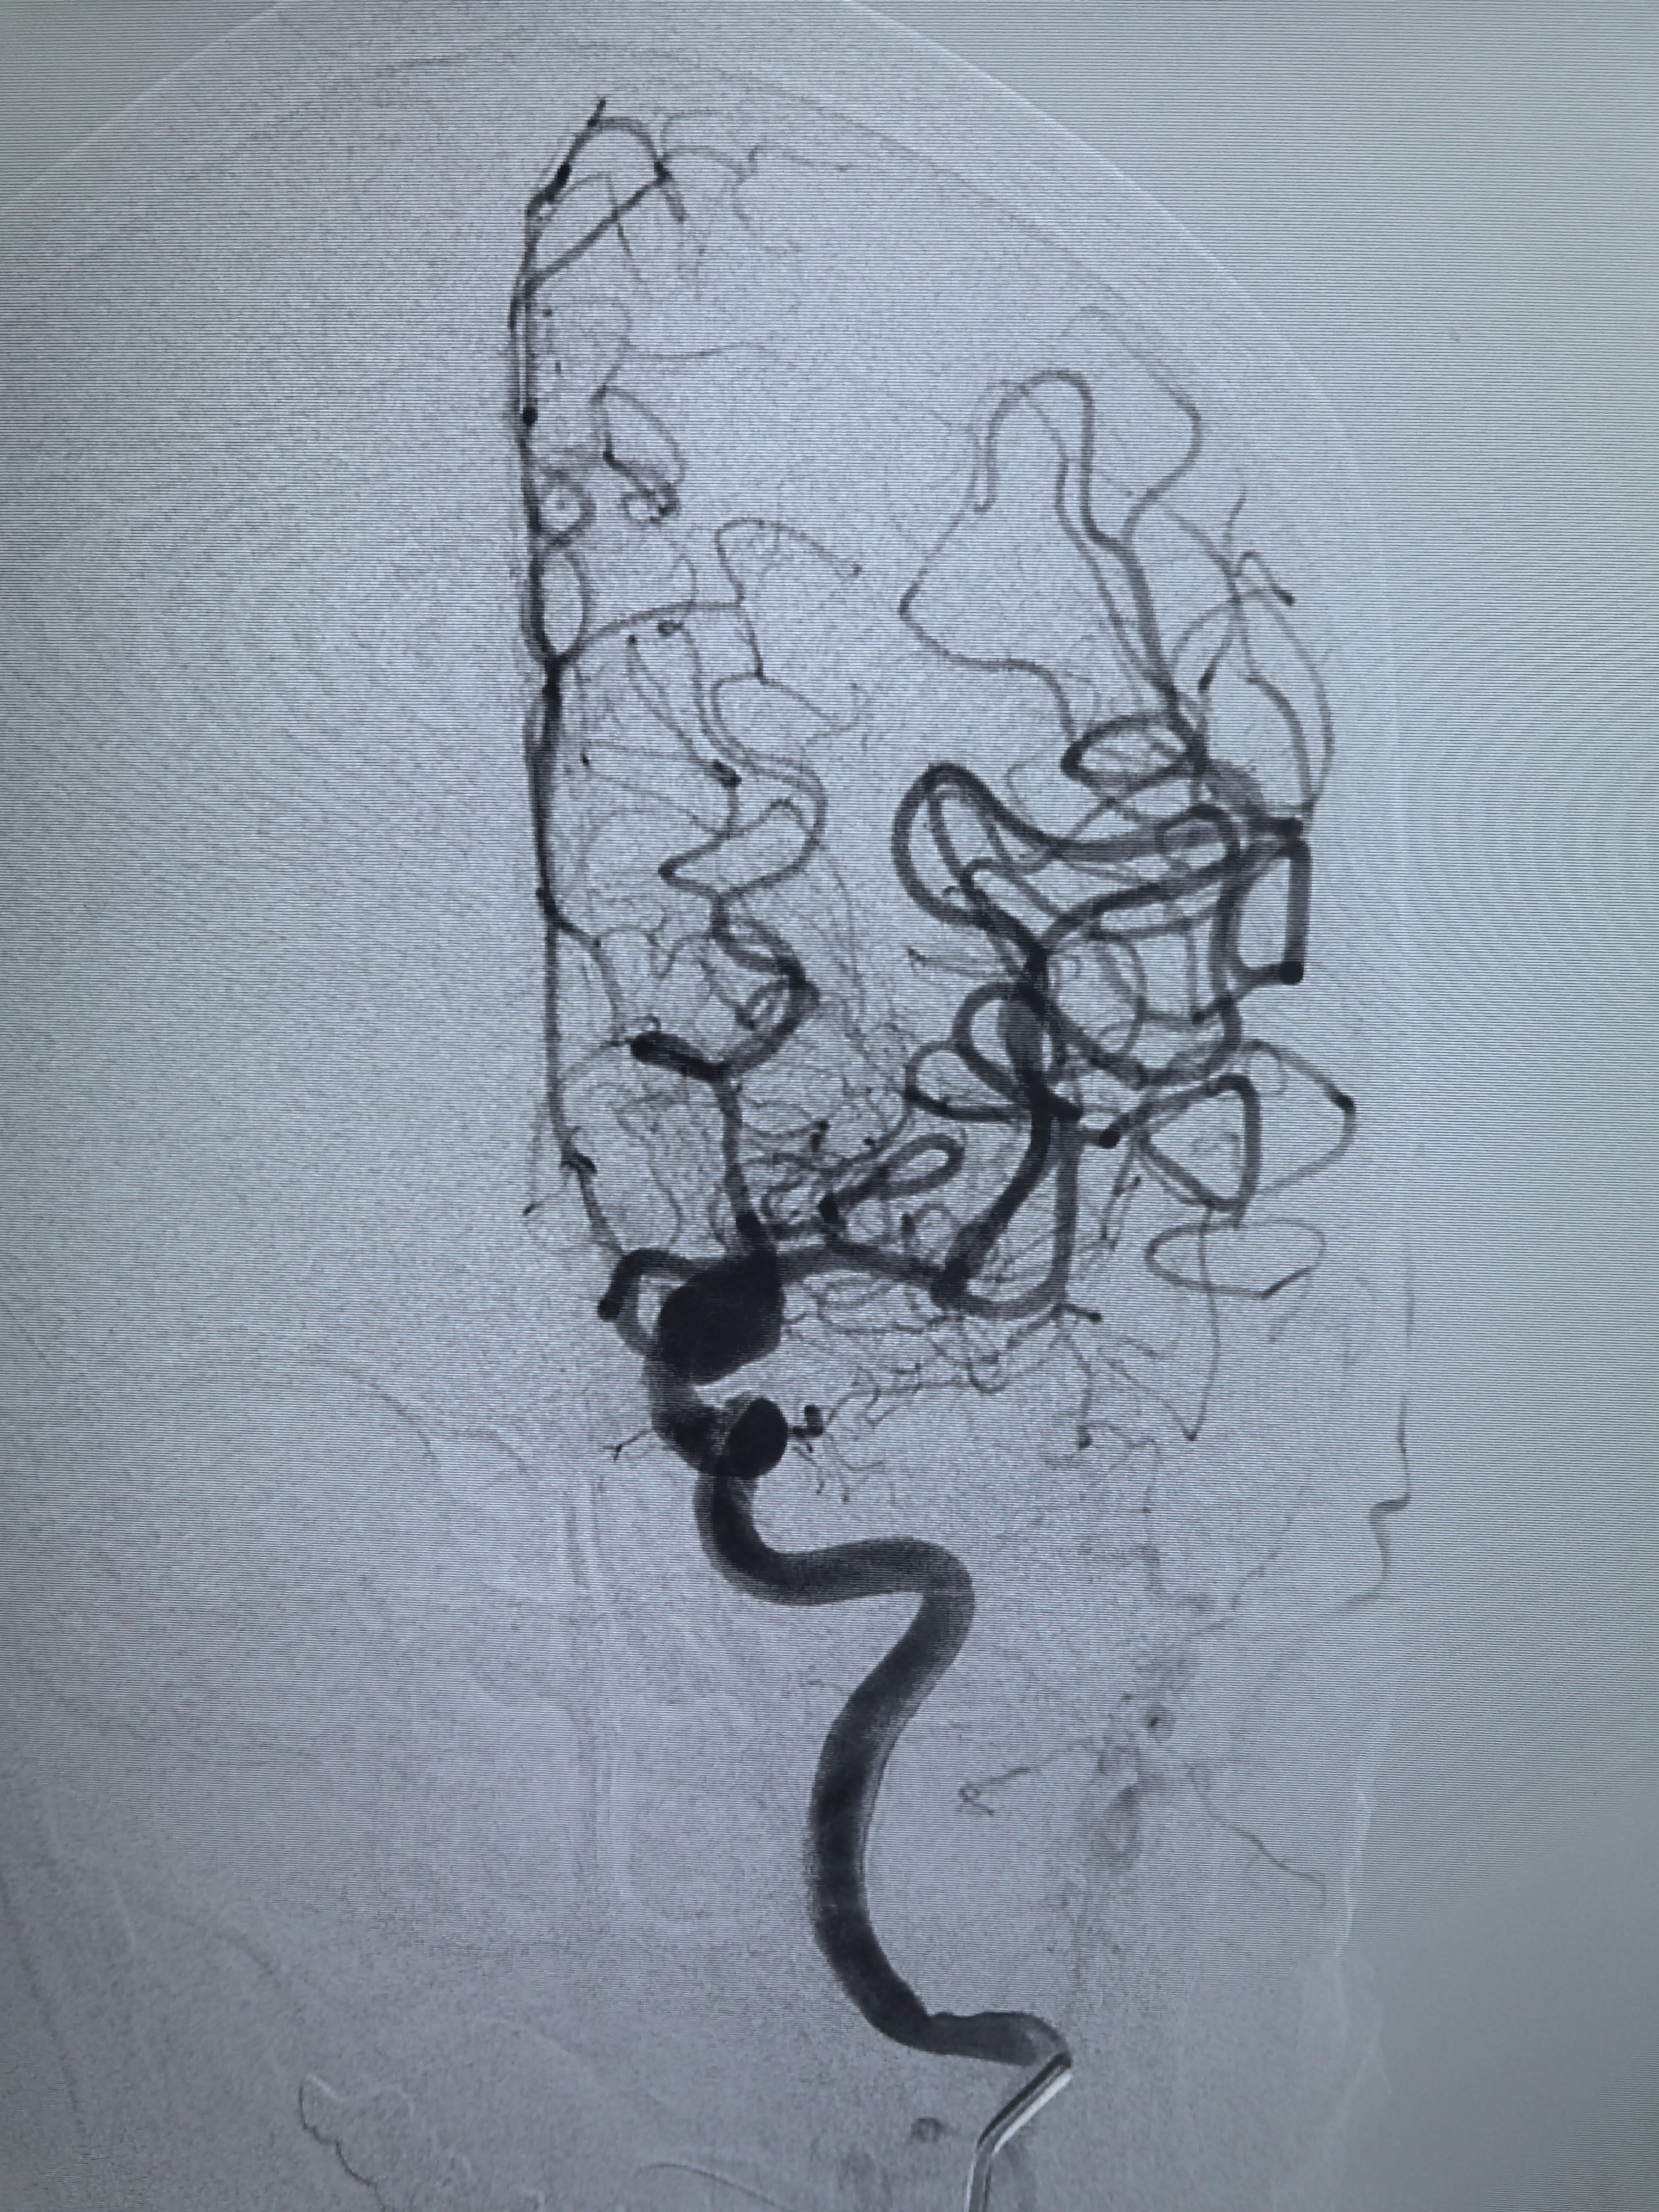

左侧颈内动脉造影!